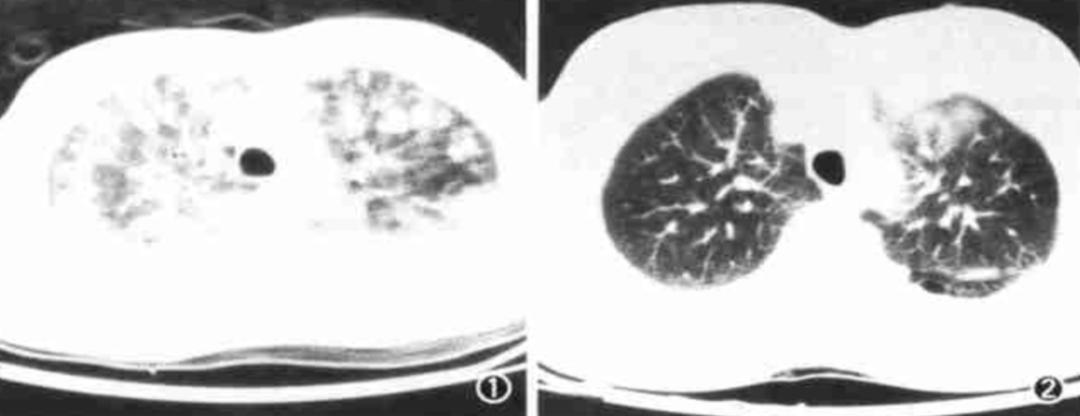

肺挫伤影像表现分为5型:

1)弥漫型:肺窗见病灶弥漫,密度稍高,边缘模糊,呈斑片、云絮状;此型又可分为病灶广泛的广泛弥漫型(图6)和较局限的局灶弥漫型(图7)。

图6(左):广泛弥漫型;图7(右):局灶弥漫型

2)分支型:病灶沿支气管分布呈分支状(图8) 。

3)团块型:肺挫伤灶较为局限,出血较多,病灶呈团块状,密度较高,边缘清晰,其内可见含气支气管征(图9)。

图8(左):分支型;图9(右):团块型